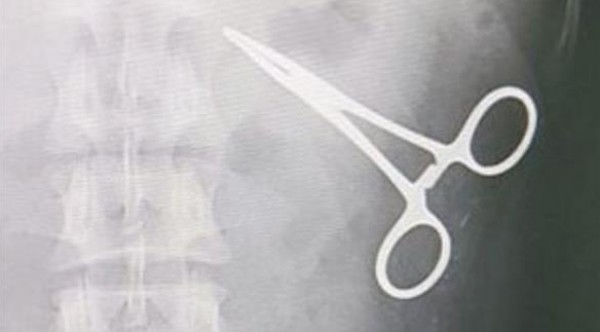

اكتشف مطار جدة مقصاً في بطن حاج عقب قدومه إلى صالة الحجاج بمطار جدة، وذلك بعدما أصدر جهاز الكشف عن المعادن صافرات أكثر من مرة.

وفي التفاصيل وفقاً لصحيفة الوطن السعودية اليوم الثلاثاء، تلقى مركز المراقبة الصحية بمطار جدة طلباً من الجهات الأمنية العاملة بصالة الحجاج بتوقيع الكشف الطبي والإشعاعي على حاج قادم من نيجيريا، بعد محاولات عدة للمرور من الصالة.

وطلب الأمن طلب من الحاج القادم إلى صالة الحجاج بمطار جدة الدولي المرور من خلال البوابة الإلكترونية للكشف عن المعادن أكثر من مرة، إلا أن الجهاز كان في كل مرة يصدر صافرات الإنذار، وعند تفتيشه لم يثبت حمله لأي آلة معدنية، فاستدعى ذلك الكشف الطبي على الجسم.

وكانت المفاجأة التي أظهرتها الصورة الإشعاعية وجود مقص معدني مستقر داخل التجويف البطني له، وبإخبار الحاج أبدى استغرابه، وبسؤاله عن سبب وجوده أبدى عدم معرفته بذلك، وذكر أنه خضع لعملية جراحية في موطنه قبل 15 عاماً، وتم إخباره بخطورة الوضع".